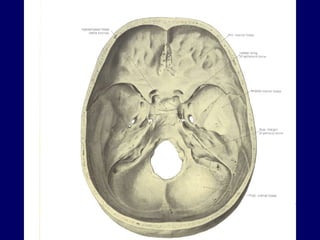

Bones are also classified according to their shape Long bones  (humerus, bones of the fingers) have a shaft and two extremities Short bones  (foot and wrist bones) more or less cuboidal in shape Flat bones  (bones forming the calvaria, sternum, scapula) Irregular bones  (facial bones and the vertebrae) Pneumatic bones  (maxilla, frontal bone) contains air cells or sinuses Sesamoid bones round or oval nodules of bones that develop in certain tendons Accessory bones develops as a result of additional ossification center or lack of   fusion (mainly in foot) Heterotopic  bones develops as a result of trauma or constant strain (thigh muscles of horseback rider)

BONE MARKINGS Surfaces of the bones are not smooth. Bones display elevations,   depressions and holes. The surface features on the bones are given names to distinguish and define them.

Linear elevation superior nuchal line, iliac crest Round elevation tubercule (small eminence), protuberance (swelling) Sharp elevation spine, process Facets area with a smooth surface where a bone articulates with another bone Rounded articular area head, condyle

Depressions fossae (small depression), groove (sulcus, long narrow depressions) Foramen hole Canal a foramen having length Orifice opening Meatus a canal entering a structure